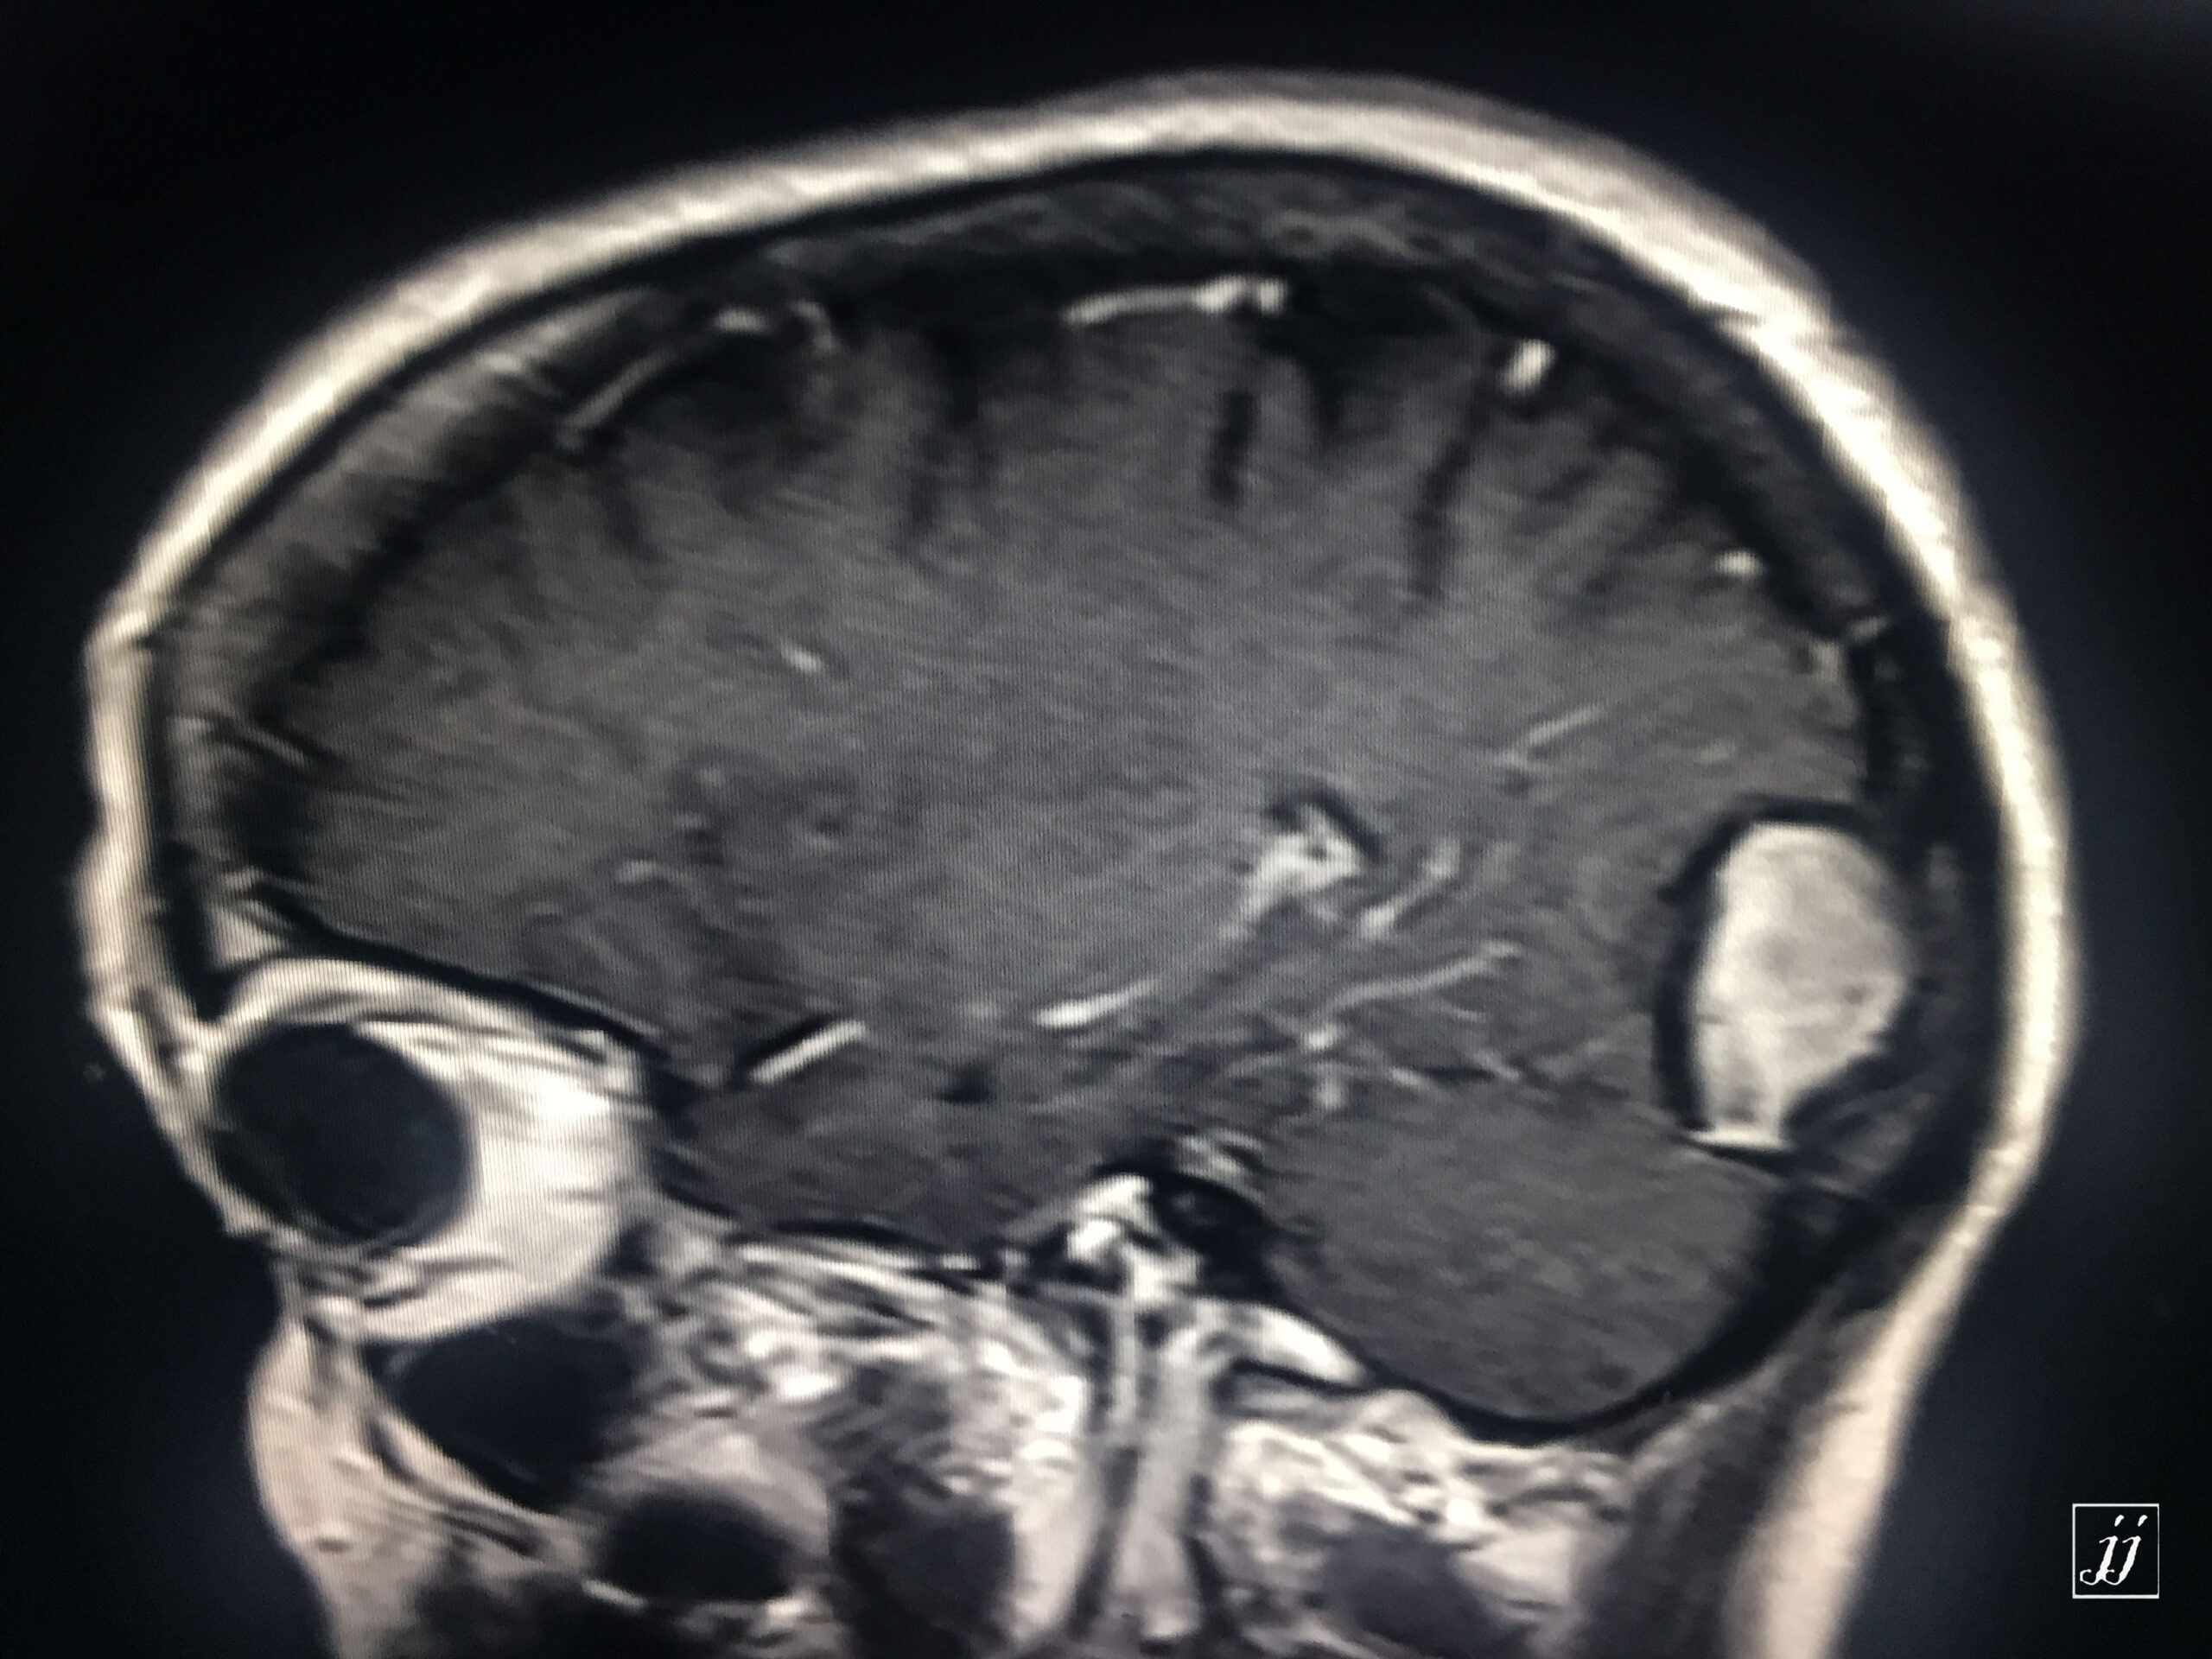

Brain- right posterior parietal old hematoma (13)